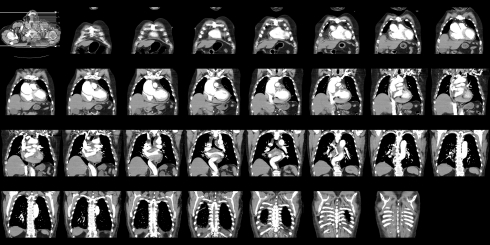

Компьютерная томография (КТ) ангиографии является изображение тест, чтобы увидеть изображения кровеносных сосудов шеи. Тест использует компьютерную томографию и введением контрастного вещества. Результаты исследования могут определить завалов, слезы и повреждение артерий шеи.